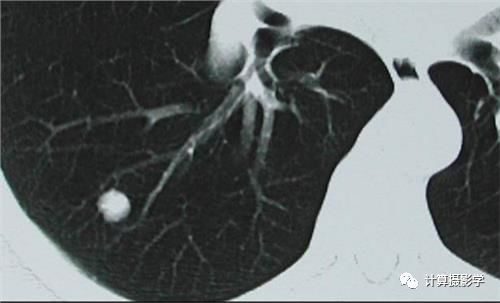

下面这张CT图片从美学上毫无美感,但是却能够清晰的揭示肺部的结节,它的图像质量高吗?